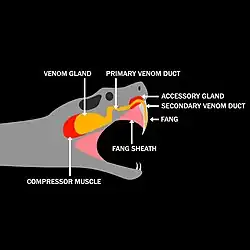

Snake venom is produced in modified parotid glands normally responsible for secreting saliva. It is stored in structures called alveoli behind the animal's eyes and ejected voluntarily through its hollow tubular fangs.

Mechanics

When venomous snakes bite a target, they secrete venom through their venom delivery system. The venom delivery system generally consists of two venom glands, a compressor muscle, venom ducts, a fang sheath, and fangs. The primary and accessory venom glands store the venom quantities required during envenomation. The compressor muscle contracts during bites to increase the pressure throughout the venom delivery system. The pressurized venom travels through the primary venom duct to the secondary venom duct that leads down through the fang sheath and fang. The venom is then expelled through the exit orifice of the fang. The total volume and flow rate of venom administered into a target varies widely, sometimes as much as an order of magnitude. One of the largest factors is snake species and size, larger snakes have been shown to administer larger quantities of venom.[86]